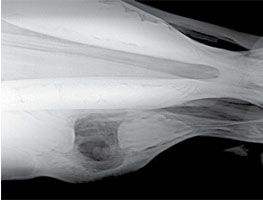

A 3-year-old Quarter horse gelding in good condition had a swelling on his right maxilla that had been increasing in size (Fig. 49). There was nasal discharge with a foul odor coming from the right nostril. The maxilla was swollen in the area of the 107, however the clinical crown looked normal when examined, and there was no mobility of any teeth in the arcade (Fig. 52). There was a small amount of feed packing on the buccal side of the 107. An open mouth lateral oblique radiograph was taken to isolate the enlarged area over the 107 (Fig. 51). Also taken was a dorsal/ventral offset radiograph showing a clear image of the abscess involving the 107 (Fig. 50). It was large and spherical in shape surrounded with dense sclerotic bone. Most root abscesses involving the upper 7’s rupture and drain to the outside of the maxilla. In this case the drain tract was formed into the nasal cavity, which is unusual. This accounts for the purulent nasal discharge coming from the right nostril. The area was surgically prepped, and local anesthesia was infused in the area to desensitize the skin and subcutaneous tissue (Fig. 53). A maxillary nerve block was performed earlier for the oral extraction which lasts approximately 90 to 120 minutes. A skin flap was created first; then the subcutaneous tissue and periosteum were elevated off the bone and transfixed proximally. A 2cm Fortner drill bit was used to make the hole through the maxilla at the proximal end of the abscess. The bone was sclerotic and thick in this area due to the chronic abscess. The hole needs to be big enough to allow a curette to be manipulated in the abscessed area. After debridement of all necrotic tissue and fragments, the periosteum, subcutaneous tissue, and skin were replaced and sutured (Fig. 54). This area should granulate in quickly if all necrotic tissue and fragments have been removed. The communication with the nasal cavity was a small drain tract that was debrided and sutured. The nasal discharge should cease if the drain tract has been resolved. The 107 was extracted orally with the horse standing using sedation and local anesthesia (Fig. 53). This tooth was not difficult to extract because of lack of reserve crown and damaged periodontal attachment. After the tooth was removed, the alveolus was examined for debris and fragments. There were numerous tooth particles about the size of small buckshot laced throughout the necrotic tissue in the abscess.